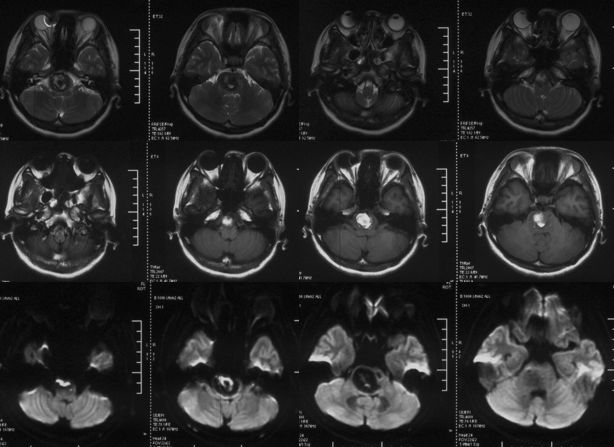

当地医院MRI:基底动脉中上段夹层动脉瘤(2019-09-16)(图4)。

图4

当地医院MRA:基底动脉中上段夹层动脉瘤(2019-09-16)(图5)。

图5